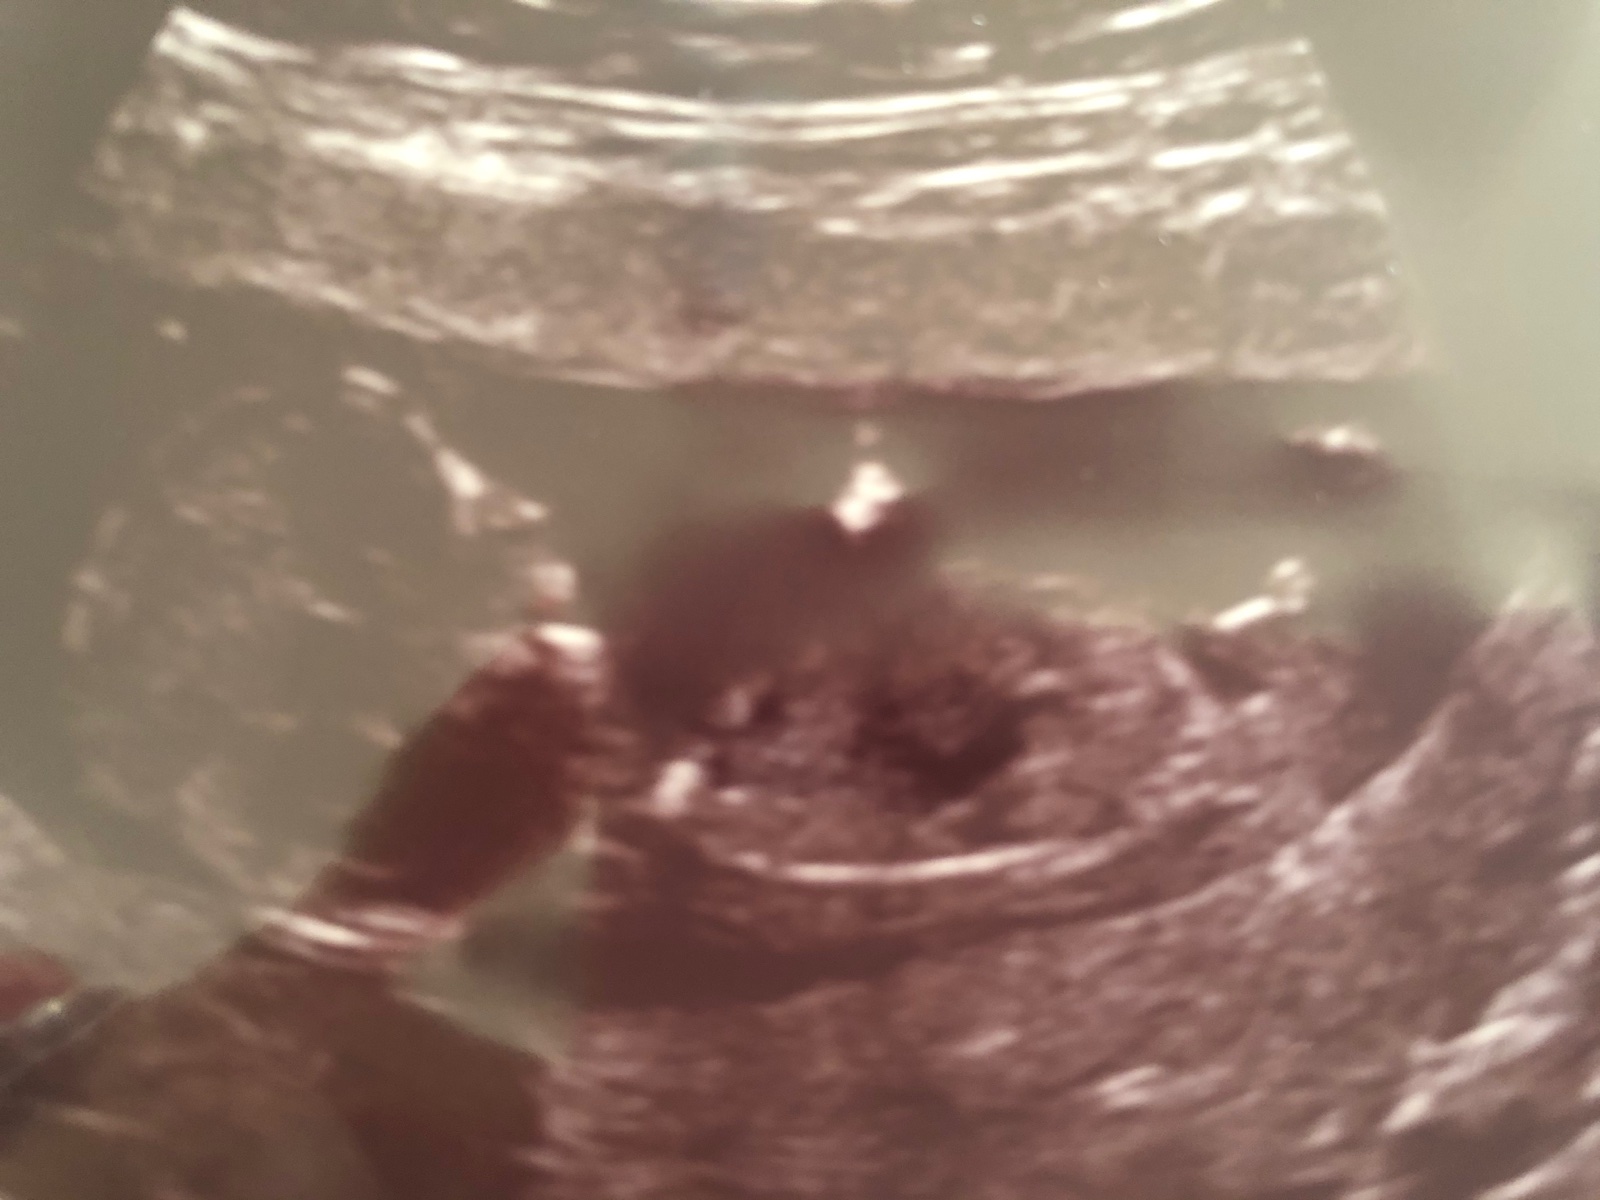

@rennye no tak ještě uvidíme, ale už počítám s druhým klukem 😁❤️

@rennye už ti další dr potvrdil chlapečka? 😀 dlouho ses neozvala 😀

@miiiissssanek taky bych řekla,že je to chlapeček

@katieb111 tady to taky vypadá na chlapečka

@juliemichal anooo, máme ho i potvrzeného, ale furt jsem si říkala, že se pan doktor také mohl splést, ale spíš to nehrozí 🤣🤣🤣